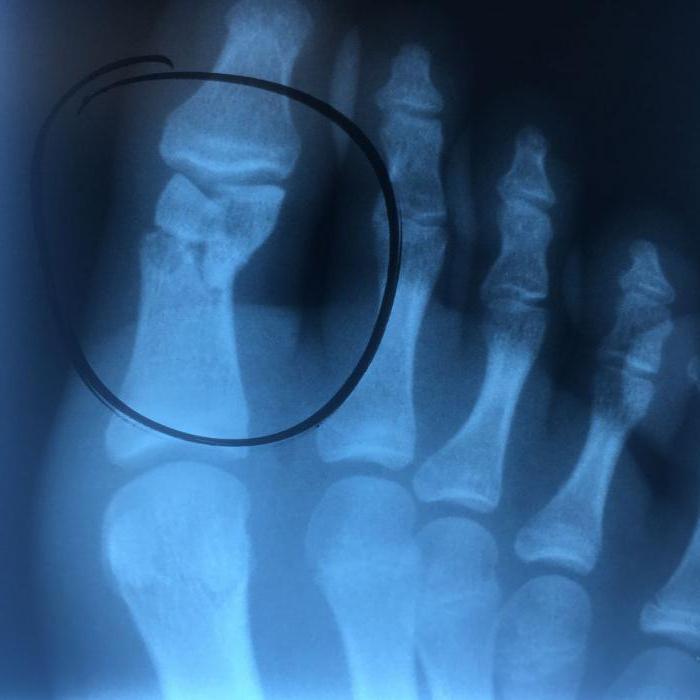

Важное значение в диагностировании переломов большого пальца ноги отдается рентгенографии ступни в одной — двух проекциях. Благодаря данному параклиническому исследованию с точностью до 95-99 % можно распознать, имеется ли травма пальца ноги, определяя с точностью до миллиметра место перелома и местоположение костных отломков.

Далее пациента направляют на рентген для получения снимка. Рентгенография необходима в нескольких проекциях. На основании снимков и предварительного обследования пациента врач делает окончательные выводы относительно характера и степени тяжести травмы.

Одномоментная закрытая репозиция применяется при переломе пальцев ног закрытого типа, сопровождающихся смещением костных отломков. Суть метода — обезболивание места перелома и последующее плавное вытягивание пальца с одновременным становлением костных отломков в их физиологическое положение.

Контролирует это рентген стопы.